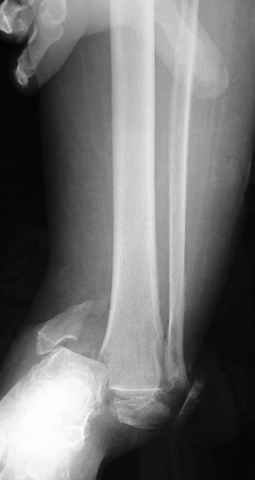

Pilon fracture:

-Появляется ориентир и остов, на чем можно строить восстановление, почему сперва малоберцовую, впервые обьяснили и описали (Pylon type and Ankle fractures) в середине 50х Rienau и Gay.

Восстановливая длину и ротацию малоберцовой кости, затем относительно легче произвести реставрацию остальных элементов перелома дистального эпиметафиза болшеберцовой кости.

где исследования на трупах показали, что малоберцовая кость участвует в стабильности голеностопного сустава, поддерживая наклон тарана (talar tilt) за счет связок. После ознакомления работой Ramsey в ортопедию ввели термин "при переломах голеностопного сустава смещенная

таранная кость следует за малоберцовой костью" т.е. связка не рвется, а тянет таран за собой, поэтому восстановление малоберцовой кости в

первую очередь, затем остальных элементов - стал классическим при лечении данной патолгии. Латеральная колонна (столб), дистальный

конец малоберцевой кости, к нему прикрепляется латеральный суставной фрагмент дистального эпиметафиза большеберцовой кости (как на снимке)

и таранная кость, которые при репозиции малоберцовой кости репонируются автоматически.

Из работ Ramsey and Hamilton, Yablon et., укорочения на 1мм

малоберцовой кости, уменьшает на 42% контактную поверхность между

малоберцевой и таранной кости, которое в свою очередь приводит к

увеличению давления на остальные части суставной поверхности, что

является предпосылкой раннего артроза.